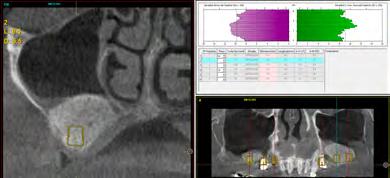

Figura 2. A. Radiografía periapical donde se observa la lesión del odontoma compuesto a nivel del maxilar superior izquierdo. B. Ortopantomografía que revela una lesión radiolúcida unilocular bien definida, con manchas de focos radiopacos, asociada con el canino superior izquierdo temporal impactado de la maxila.

El examen clínico reveló un aumento de volumen en la zona de órganos dentarios 63-65 que se extendía al seno maxilar, con desplazamiento de cortical vestibular, sin perforación ni cambio de color en la mucosa, de estructura uniforme bien delimitada. (Figura 1). En el examen radiográfico se observó la expansión de la cortical, con la presencia de múltiples dentículos. Desplazamiento del órgano

dentario 63 hacia el seno maxilar (Figura 2).

Radiográficamente estas lesiones presentan un área radiolúcida bien definida que contiene cantidades variables de material radiopaco de irregular tamaño y forma. La extensión de las áreas radiopacas y radiolúcidas difieren de una lesión a otra, dificultando muchas veces su diagnóstico radiológico en ocasiones la

cantidad de material mineralizado predomina semejando un odontoma complejo. El tumor puede producir una expansión variable de las corticales y encontrarse asociado a una pieza retenida, a la cual puede desplazar o interferir en su erupción.13